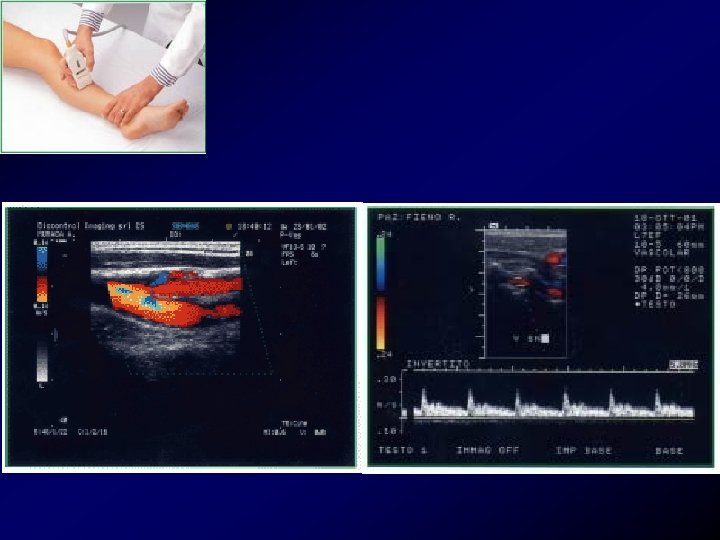

Diagnosi: Esami ecografici • L’ecografia o meglio l'eco color Doppler venoso, deve essere subito disponibile per non rallentare il processo di conferma diagnostica, può documentare una TVP dell'asse femoro-iliaco, sensibilità 93%, specificità 98%.